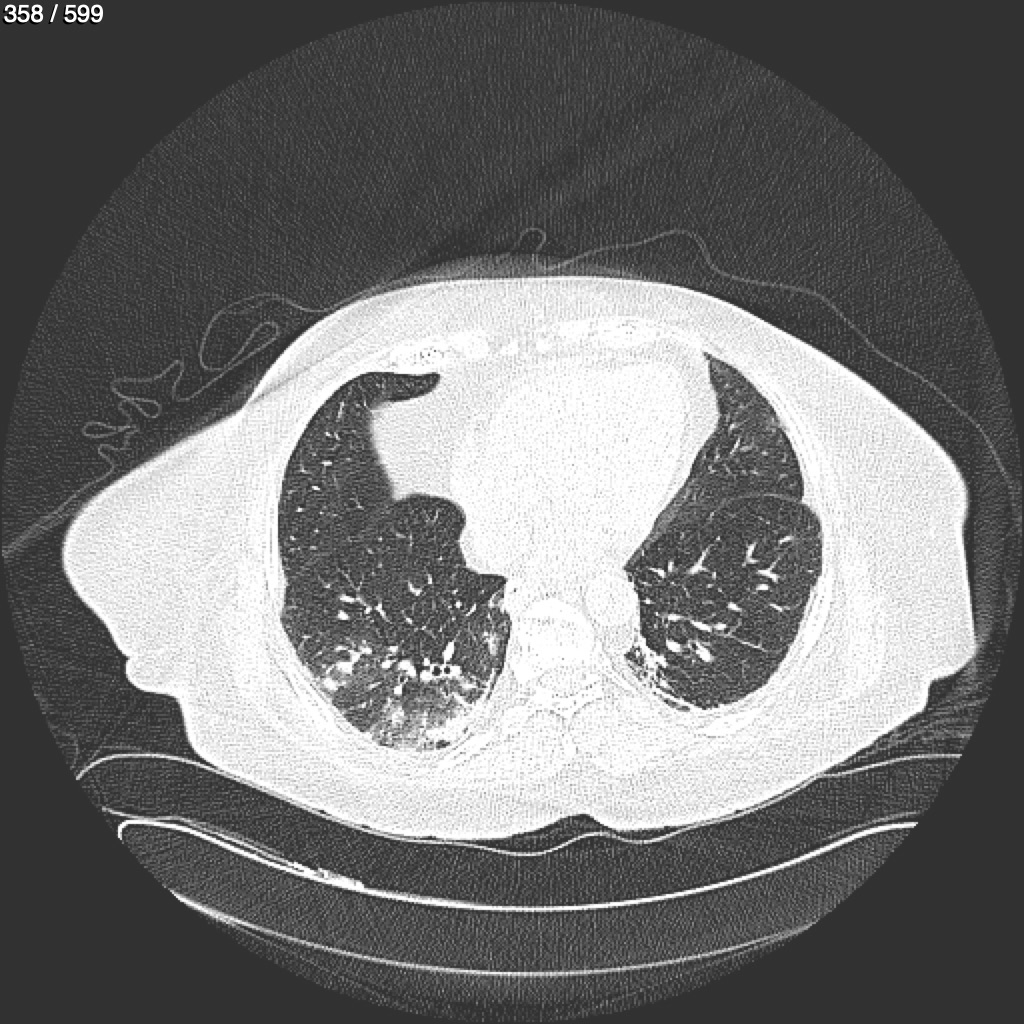

Home G​l​o​r​i​a​ ​G​l​a​d​y​s​ ​B​e​a​s​l​e​y​ ​-​ ​T​ó​r​a​x​ ​T​o​r​a​x​_​S​i​m​p​l​e​ ​(​A​d​u​l​t​o​)